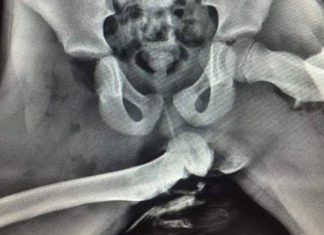

Suka letak kaki atas papan pemuka? Gambar X-ray ini mungkin mengubah tabiat anda

Anda sudah pasti tahu bahawa penumpang kereta yang meletakkan kaki di atas papan pemuka adalah kelakuan yang tidak selamat.

Kecederaan yang serius mungkin boleh dialami...